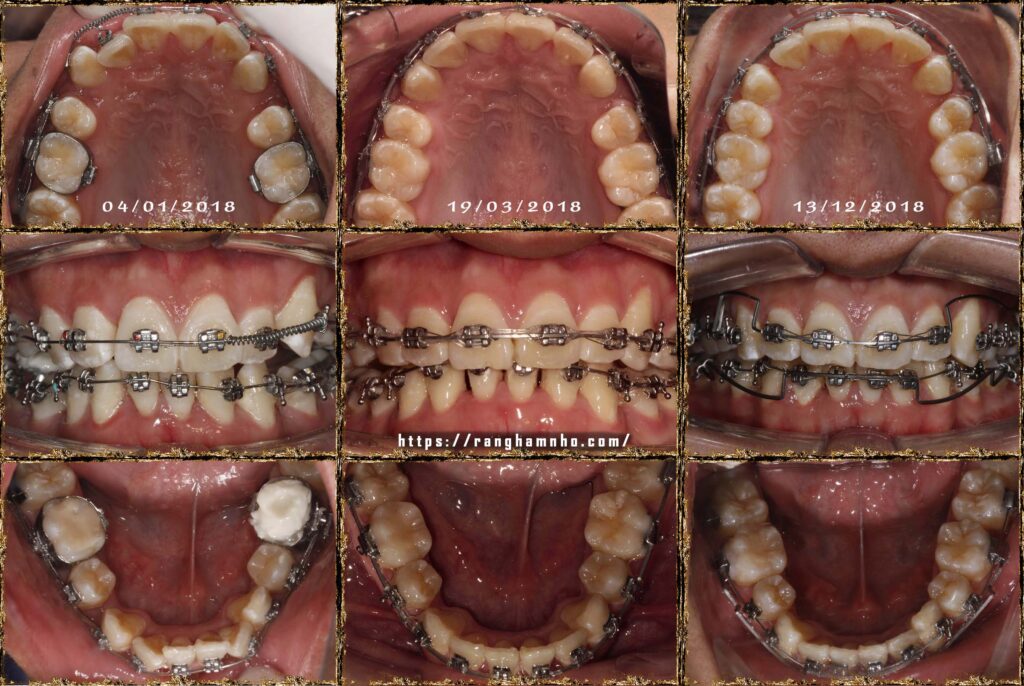

Bệnh nhân nam sinh năm 1998. Khớp cắn hạng I, với chen chúc và khấp khểnh nặng ở cả 2 hàm trên và dưới.

Cung hàm trên và cung hàm dưới đều hẹp, răng thiếu chỗ nghiệm trong.

Kế hoạch: Nhổ 4R4, chỉnh nha phân đoạn

Làm phẳng mặt phẳng cắn bằng cung tiện ích TMA 17×25 hai hàm